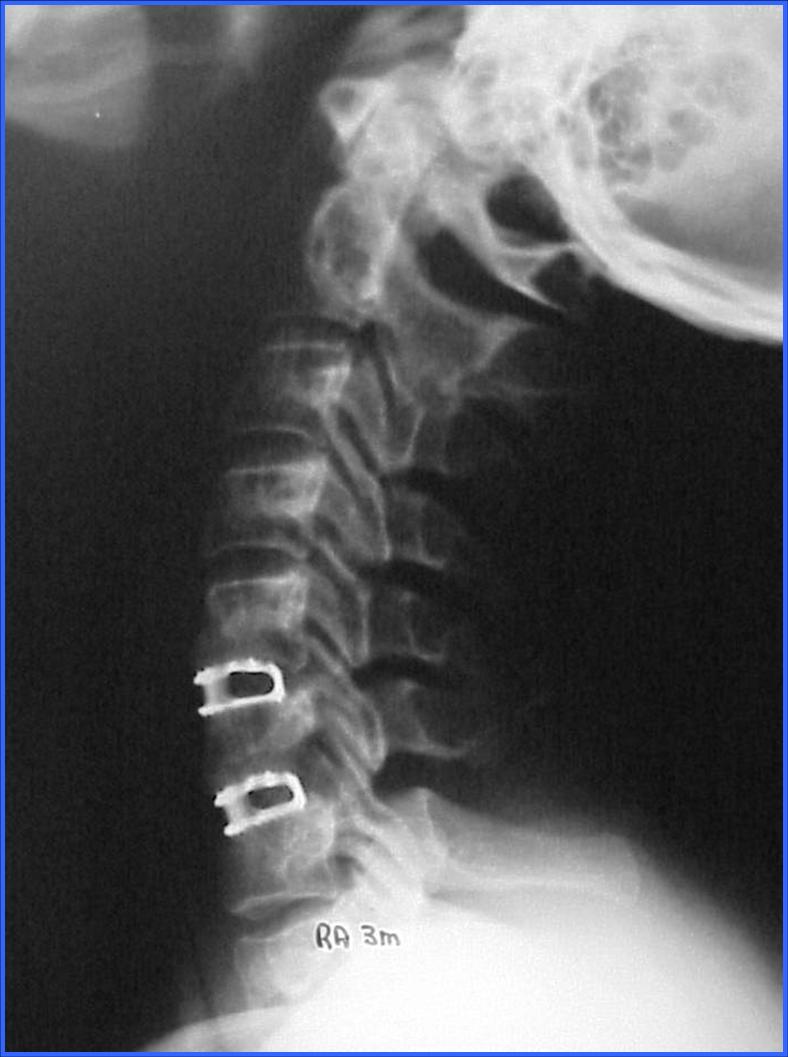

El otro problema más frecuente en la columna cervical es el dolor discogénico, el diagnóstico se hace con el examen Clínico y la Resonancia Magnética. El tratamiento es conservador, pero en los casos refractarios es necesario sustituir el disco por un espaciador biocompatible.